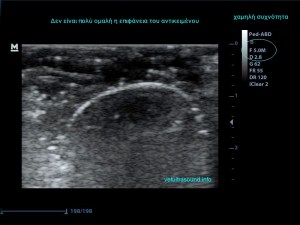

3) Τη συχνότητα, δηλαδή όσο πιο μεγάλη είναι αυτή, τόσο πιο πολλές λεπτομέρειες βλέπουμε αλλά ταυτόχρονα αυξάνονται τα τεχνουργήματα από αέρα και άλλες δομές. Οι αρμονικές βοηθούν στην καταστολή αυτών των τεχνουργημάτων.